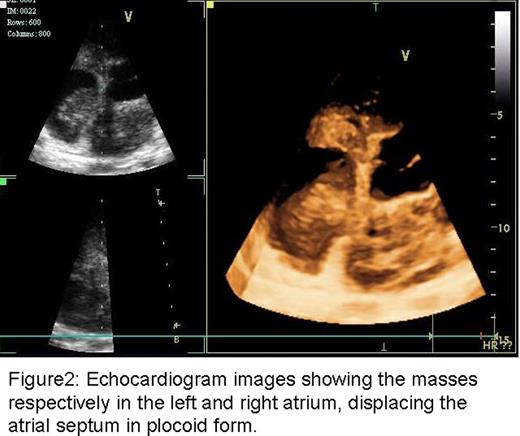

A 33-year-old man of Asian descent was admitted to our hospital 3 years ago with a main complaint of palpitations for 7 months. There was no fever, no cough, no gain or loss of weight, no night sweats, no medical history of allergic diseases or contact with parasites. Physical examination showed marked edema in the neck and upper chest, and the hepatojugular reflux was positive. There was no change in skin appearance or hepatosplenomegaly. A soft rubbery, non-tender lymph node (1×2cm) was palpated in the left axillary area. The laboratory data showed mild eosinophilia (leukocyte count 6000 /ul with eosinophils 582/ul). The serum IgE concentration was increased (1,250 U/ml). Serological tests for HBsAg, anti-HCV, anti-HIV, and antibodies for distoma pulmonala, distoma japonicum, schistosome, bladder worm, sparganum, trichina cystica and filarial were negative, however toxoplasma gondii antibody IgG was positive, while the IgM was negative. Antinuclear antibodies were all negative. Echocardiogram revealed a mass (7.1×7.0×5.5cm) displacing the base of the heart and involving both atria. CT showed enlarged biaxillary lymph nodes and a large mediastinal mass extending into both atria and obstructing the superior vena cava with right ventricular hypertrophy (Fig.1a, b). Positron emission tomography (18F-FDG-PET) scan indicated negative fluorodeoxyglucose (FDG) uptake in the lymph nodes, spleen and liver. Biopsy of an enlarged right axillary lymph node was performed and the pathology revealed a normal preserved nodal architecture with proliferation of lymphoid follicles infiltrated by abundant eosinophils partially forming eosinophilic microabscesses. CD20 staining was positive. The bone marrow examination indicated normal cellularity except a little increase of eosinophils at 7.5%. Biopsy of the cardiac mass was not performed due to technical challenges related to its anatomical location. Based on the clinical and laboratory findings, a diagnosis of Kimura disease was established. Treatment was started with a low dose of oral prednisone 20–30mg/d. After treatment, the enlarged lymph nodes diminished gradually. However, 4 months later, echocardiogram showed the mediastinal mass remained, with two new masses (left 5.4×3.2cm, right 4.3×2.6cm) attached to the atrial septum respectively (Fig2). Prednisone was gradually increased to 50mg/d. 3 months later, the patient was admitted to hospital with chest pain and shortness of breath. Thoracic CT showed severe obstruction of the right middle lobe bronchus by the enlarged mediastinal mass. A bone marrow smear and flow cytometric analysis did not show any clonal hematopoietic abnormality. The echocardiogram remained unchanged. Prednisone (40mg/d) was re-administered but the patient's situation was getting worse quickly. He developed dyspnea and hypoxemia, apparent SVCS, edema of the inferior extremities and recurrent arrhythmia. CHOP chemotherapy was initiated (CTX 1.0 dl, VDS 4mg dl, EPI-ADM 60mg dl, DXM 10mg dl-2) but he died due to cardiac and respiratory failure. Kimura's Disease is a distinct clinicopathological entity accompanied by peripheral blood eosinophilia and elevated serum IgE level. Though rare, KD with cardiovascular involvement has been reported in several cases. This kind of involvement is also named as Eosinophilic Myocarditis (EM), occurs in up to 60% of patients diagnosed with hypereosinophilic syndrome (HES). However, this patient only has partial response of prednisone, and relapsed after 9 months therapy with prednisone 20–50 mg/d. Although chemotherapy was added, it was too late to control the progression of disease. This instructive case demonstrates that although Kimura's disease is a benign process, infiltration of eosinophils in multiple organs may result in critical illness and can be fatal. Early intervention and frequent close followup appears essential for controlling disease in KD patients with cardiac or other critical complications.